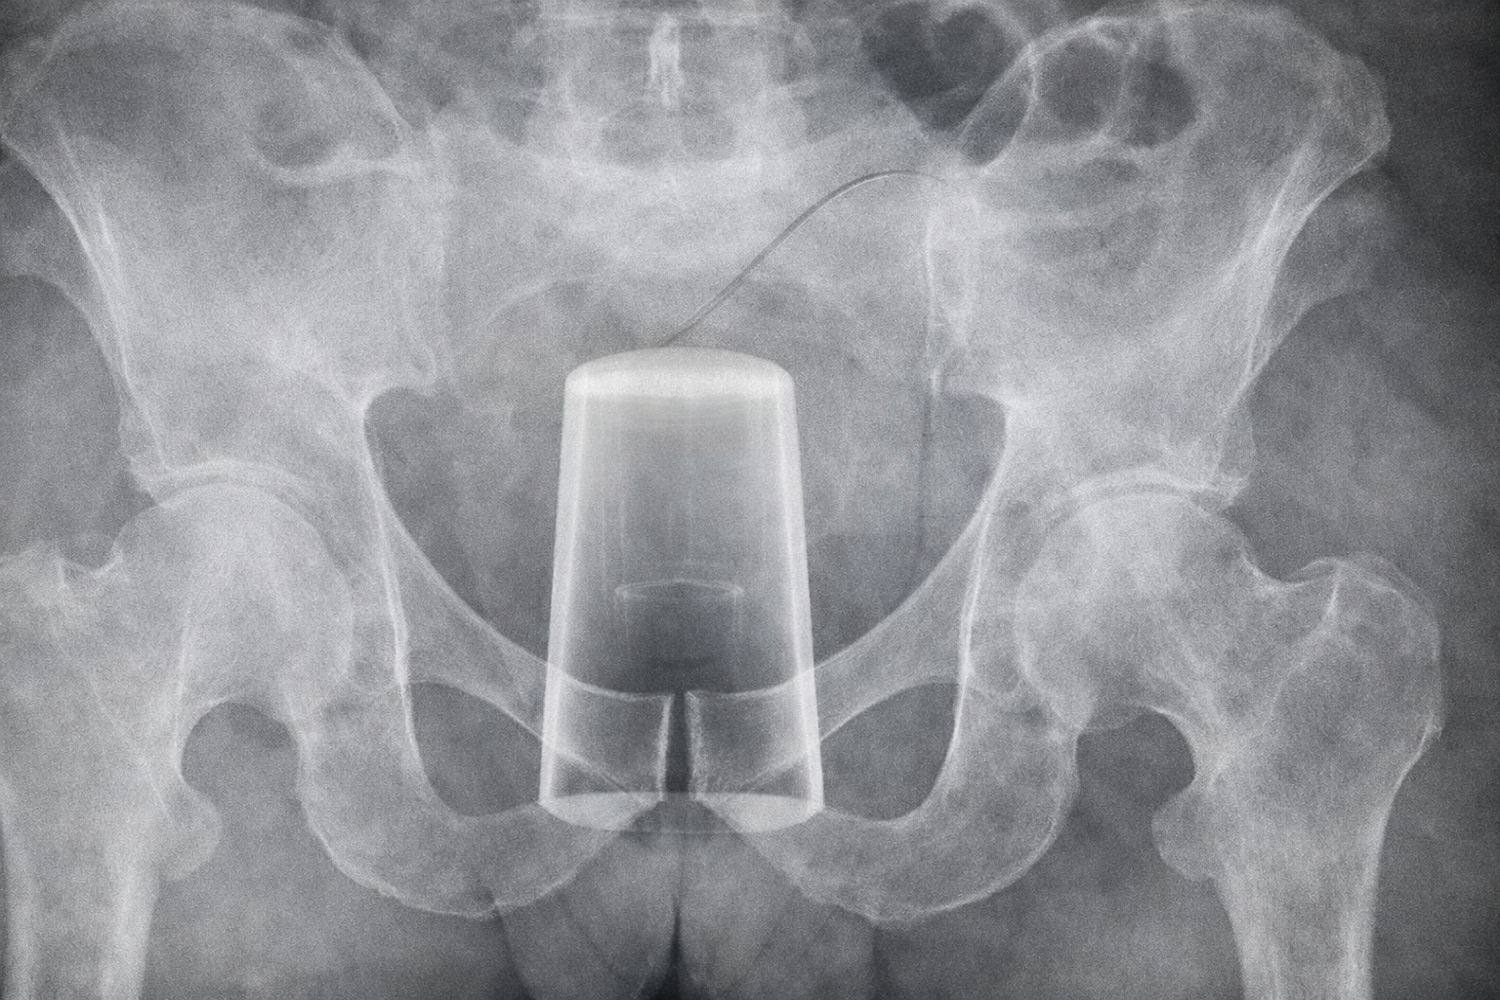

Dabei soll es passiert sein. Nach eigenen Angaben "rutschte" Dmitri aus und "stürzte" auf ein Trinkglas. Mit dem blanken Anus.

Das Glas drang in seinen Körper ein. Er konnte den mit roten Blumen verzierten Fremdkörper nicht mehr selbst entfernen. Der Rettungsdienst musste anrücken.

Im Krankenhaus wurde der unglückliche Russe operiert. Danach wurde er mit dem Rat nach Hause geschickt, einen solchen Stunt doch bitte nicht zu wiederholen und sich regelmäßig zu Nachuntersuchungen einzufinden.